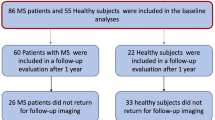

In total, 40 subjects with early RRMS and 15 age-and-sex-matched HCs were included in the study. A total of 11 subjects did not complete both year-1 and year-2 measurements and were, therefore, excluded from analyses in the current study (two HC subjects [inability to undergo MRI examination] and nine RRMS subjects [n = 5 switch to second-line therapy; n = 1 switch to first-line therapy just prior to examination; n = 3 inability to undergo MRI examination unrelated to RRMS]). This resulted in a total of 44 age-, sex-, and education-matched subjects (13 HC, 31 RRMS) with full data available for analysis, for whom demographics are depicted in Table 1. Follow-up time for RRMS and HC subjects was similar (1.00 ± 0.10 years and 0.99 ± 0.10 years, respectively).